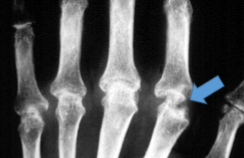

Rheumatoid Arthritis

Juxta-articular erosions (lysis of bone/osteopenia)

Joint ankylosis

Juxta-articular bone erosions